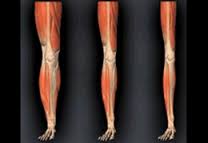

As early as your 30’s you begin to experience sarcopenia http://www.webmd.com/healthy-aging/sarcopenia-with-aging

“Although sarcopenia is mostly seen in people who are inactive, the fact that it also occurs in people who stay physically active throughout life suggests there are other factors involved in the development of sarcopenia.”

A common consequence our society has gotten far too use to is simply allowing themselves to slow down and begin to suffer poor health. You get use to this slow degradation of the way you feel and look and accept your fate (perhaps because it is so slow). The less bone density, connective tissue strength and lean muscle you have…the less you can physically do. The inevitable result is there then becomes less of a reason for the rest of you to stay vital. The dwindling draw on your system to output energy and move with zest feeds this fading and fumbling of ability.